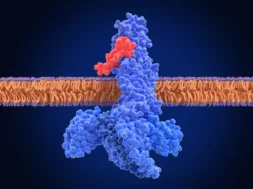

Η κλινική δοκιμή φαίνεται να επιβεβαιώνει τη θεωρία ότι η απομάκρυνση των ‘πλακών’ της πρωτεΐνης βήτα αμυλοειδούς από τον εγκέφαλο των ασθενών σε αρχικό στάδιο Αλτσχάιμερ (κάτι που επιτυγχάνει το νέο φάρμακο στοχεύοντας την εν λόγω πρωτεΐνη προτού αυτή δημιουργήσει τοξικές συσσωματώσεις), μπορεί να καθυστερήσει την εξέλιξη της νόσου. Από την άλλη, το φάρμακο εμφανίζει αυξημένη πιθανότητα παρενεργειών, όπως πρήξιμο του εγκεφάλου και μικρο-αιμορραγίες, που όμως θεωρούνται ανεκτές.